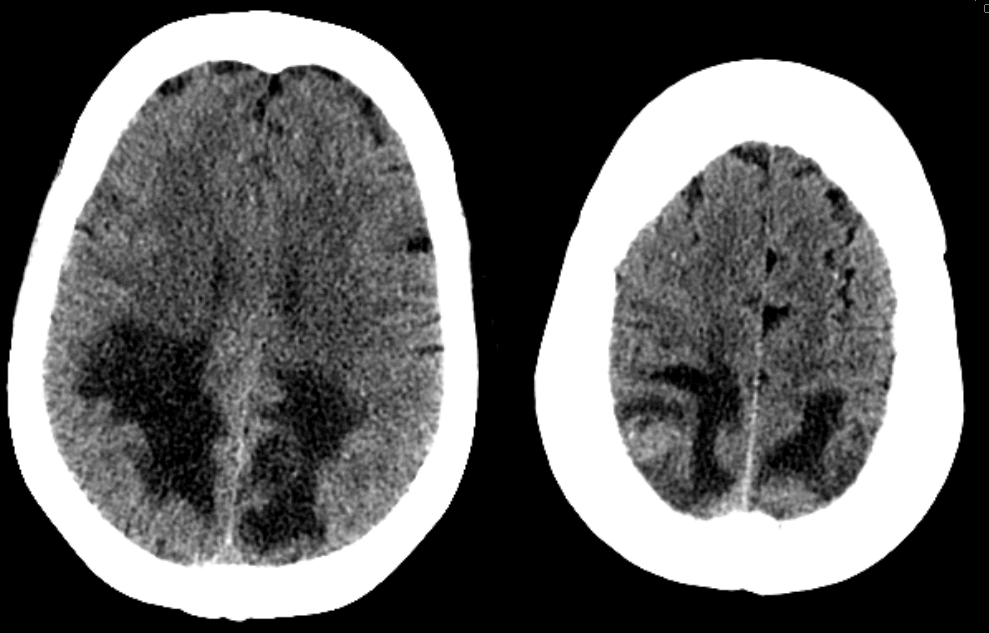

Case history: 55 year old female with history of lung adenocarcinoma presents with difficulty seeing. She was treated with carboplatin and paclitaxil two months prior to admission. CT head showed hypodensities in bilateral posterior white matter, as shown below. What is your diagnosis?

Initial interpretation based on posterior hypodensity was like PRES (Posterior Reversible Encephalopathy Syndrome) especially given recent paclitaxel and carboplatin use (both of which have been associated with PRES). Subsequent MRI with and without contrast, however, showed multiple enhancing lesions, suggesting metastatic disease without PRES.